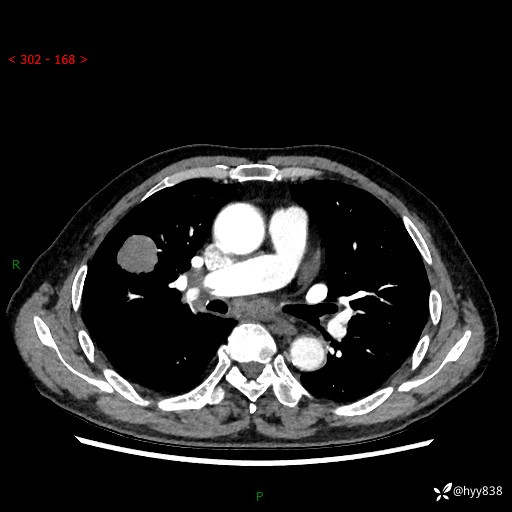

69岁/男,间断咳嗽伴气促、下肢水肿。临床拟诊肺栓,偶发肺均质强化结节--结果公布

【患者信息】:69岁/男

【主诉】:间断咳嗽伴气促、下肢水肿2周

【现病史及既往史】:患者2周来无明显诱因出现咳嗽,咳少量白痰,不易咳出,伴有气促,呈间断发作,症状与活动费力相关,以夜间为甚,不能平躺入睡,偶有憋醒,无胸闷胸痛、无发热、无头晕、头痛等不适,伴有双下肢中度水肿,就诊于当地县人民医院门诊,完善相关检查提示:左下肢深静脉血栓形成,未予以特殊处理,今患者为求进一步诊治来我院就诊,拟“心衰”收入我科。 起病以来,患者精神、饮食、睡眠可,大小便如常,体力明显下降,体重未见明显减轻。

【检查】:胸部CT增强